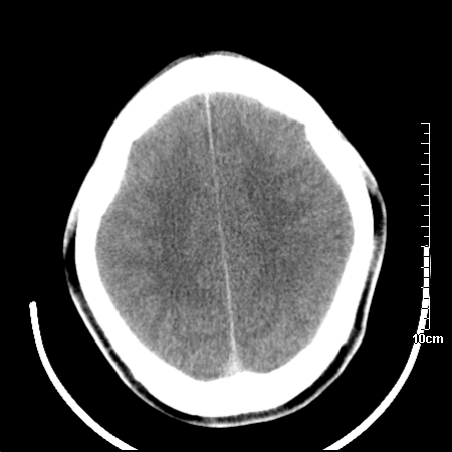

头晕.头痛间断意识恍惚1周 m/21y

4天上述症状加重伴左侧肢体发软,复查ct,

右侧放射冠可见点状低密度,可疑腔隙性梗塞

我当时诊断的是1.右侧底节区脑血栓形成

2.考虑少量蛛网膜下腔出血

3.右侧颞叶低密度区考虑脑血管畸形

因病人拒绝进一步检查,反复做工作后,病人做了腰穿,脑脊液化验显示有红细胞,呈现轻度红色

右側额叶、放射冠区灰白质改变,建议ct增强或mri检查

右侧放射冠区混杂密度灶,边缘不清,病人较年轻,结合有发热病史,支持感染性病变,建议密切结合临床可抗感染治疗后复查。

右侧颞叶病变定性困难,既然发病急,又有发热,脑脓肿不能除外。

右侧颞叶混杂密度灶,强烈建议:增强ct检查